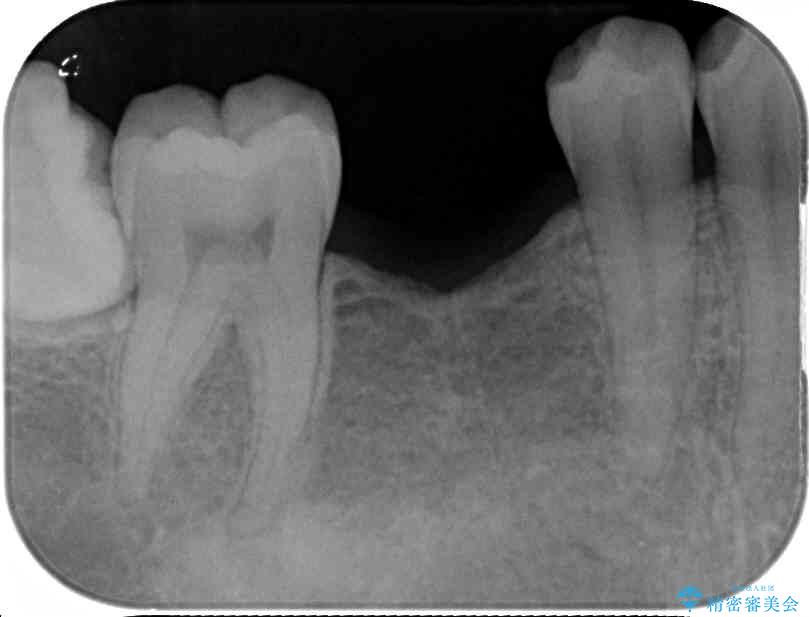

治療前

• 空いている時間を利用して通院 奥歯のインプラント治療 治療前画像